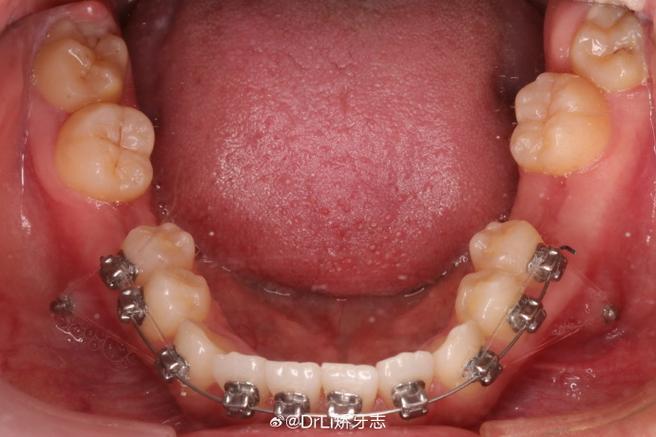

(图片来源网络,侵删)- 转矩控制不当: 在排齐和内收阶段,如果使用的托槽转矩角度设置过大(即托槽本身带有过大的舌向转矩),或者医生在施加内收力时没有有效控制牙齿的转矩(即牙齿在向后移动时同时向舌侧倾斜),就容易导致下牙内倾。

(图片来源网络,侵删)- 清洁困难: 舌倾的牙齿之间以及牙齿与舌侧牙龈之间容易堆积食物残渣和菌斑,增加龋齿和牙龈炎、牙周炎的风险。